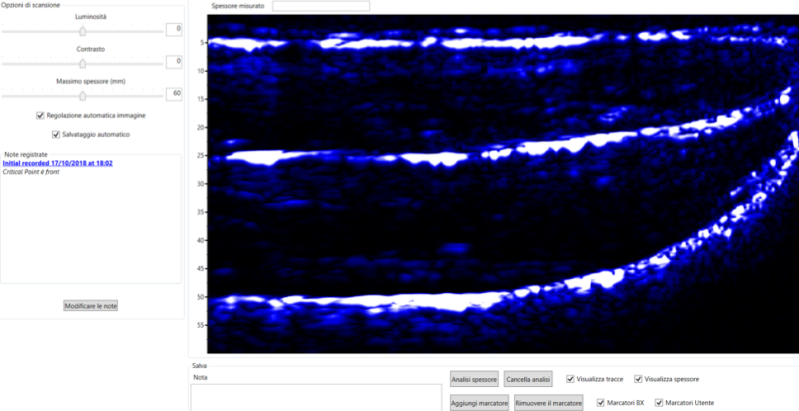

L’esame viene effettuato in pochi minuti, utilizzando un gel per ultrasuoni. L’adipometro viene fatto scorrere normalmente sull’addome e sulla coscia, e su altre eventuali zone del corpo che possono essere di interesse al professionista sulla base delle caratteristiche del paziente. L’apparecchio ci restituisce immediatamente un’immagine ecografica del distretto analizzato come nella immagine a fianco.